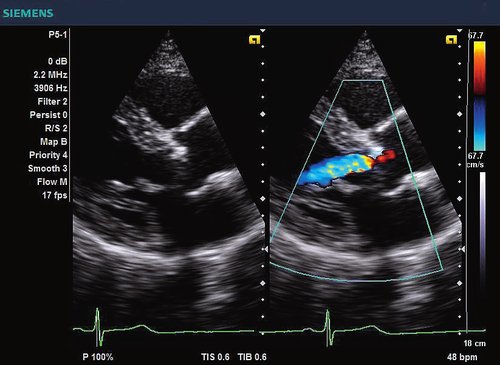

Siemens ACUSON X300 PE Beschreibung

• Features: 3D, 4D, Farb/Doppler

• Kardiologie